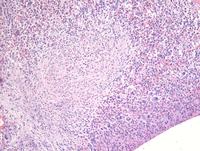

A 70-year-old man presented with persistent eosinophilia. Hb 133 g/L, WBC 70 x10^9/L, Neutrophils 57 x10^9/L, Eosinophils 15.7 x10^9/L, platelet 186 x10^9/L. Bone marrow aspirate is hypercellular. Granulopoiesis is hyperplastic with no excess of blasts.  Eosinophils and precursors are markedly increase accounting for 65% of total nucleated cells.  Some have abnormal lobulation, cytoplasmic vacuolation and patchy granulation. BCR-ABL and JAK2 were negative by PCR. Leukaemia fusion gene (Q30) screen was positive for the FIP1L1-PDGFRA translocation. FISH indicates loss of CHIC2 at 4q12. Other hematologic neoplasms or reactive eosinophilia were excluded.